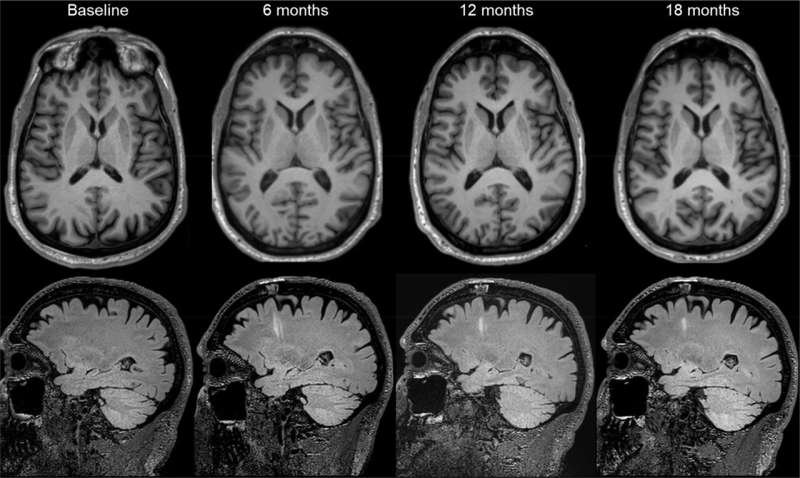

代表性磁共振圖像。圖片來(lái)源:《自然》(2025)。DOI:10.1038/s41586-025-08845-y

第二項(xiàng)試驗(yàn)在美國(guó)和加拿大各地進(jìn)行,Viviane Tabar及其同事探究了源自人類胚胎干細(xì)胞的多巴胺能神經(jīng)元祖細(xì)胞產(chǎn)品(bemdaneprocel)的安全性。12名患者(平均年齡67歲)接受了手術(shù),將bemdaneprocel移植到大腦兩側(cè)的殼核。5名參與者接受了低劑量(每核0.9百萬(wàn)個(gè)細(xì)胞),7名參與者接受了高劑量(每核2.7百萬(wàn)個(gè)細(xì)胞)。

該細(xì)胞產(chǎn)品總體耐受性良好,在18個(gè)月的隨訪期內(nèi)未報(bào)告與治療相關(guān)的嚴(yán)重不良事件。此外,未出現(xiàn)此前用于治療帕金森病的胎兒組織移植相關(guān)運(yùn)動(dòng)障礙的發(fā)生。